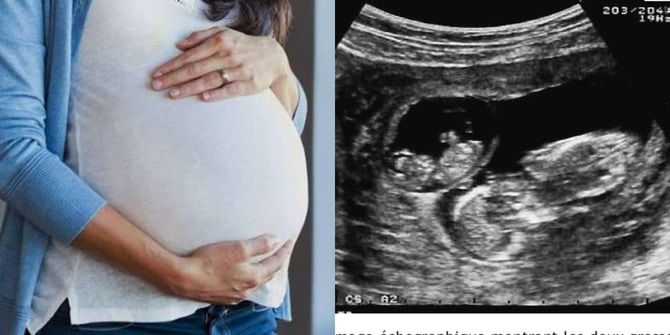

Tanda superfetation berlaku

Biasanya situasi ini akan dapat dikesan semasa ujian ultrasound di klinik atau hospital. Doktor dapat mengenal pasti jika ada kehadiran dua janin. Namun janin-janin itu mengalami perkembangan dan pertumbuhan yang sangat berbeza daripada segi saiz dan kematangan.

Anda mungkin akan dirujuk kepada doktor pakar jika dikesan anda mengalami superfetation kerana risikonya juga agak tinggi bagi kandungan seperti ini.